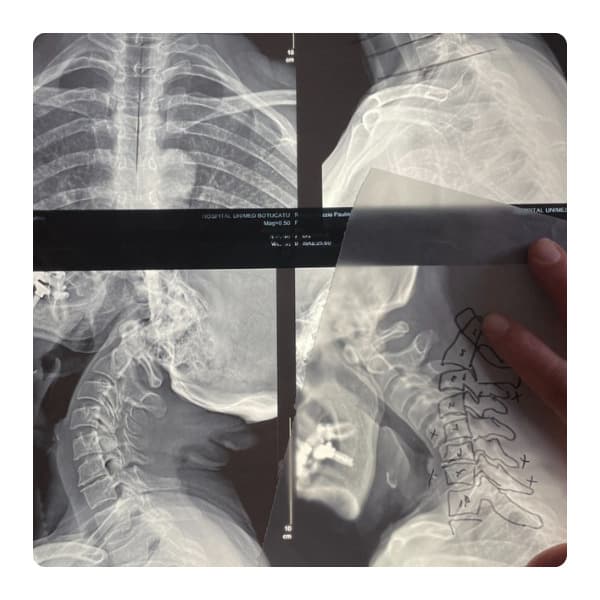

Análise detalhada da curvatura e alinhamento da coluna vertebral.